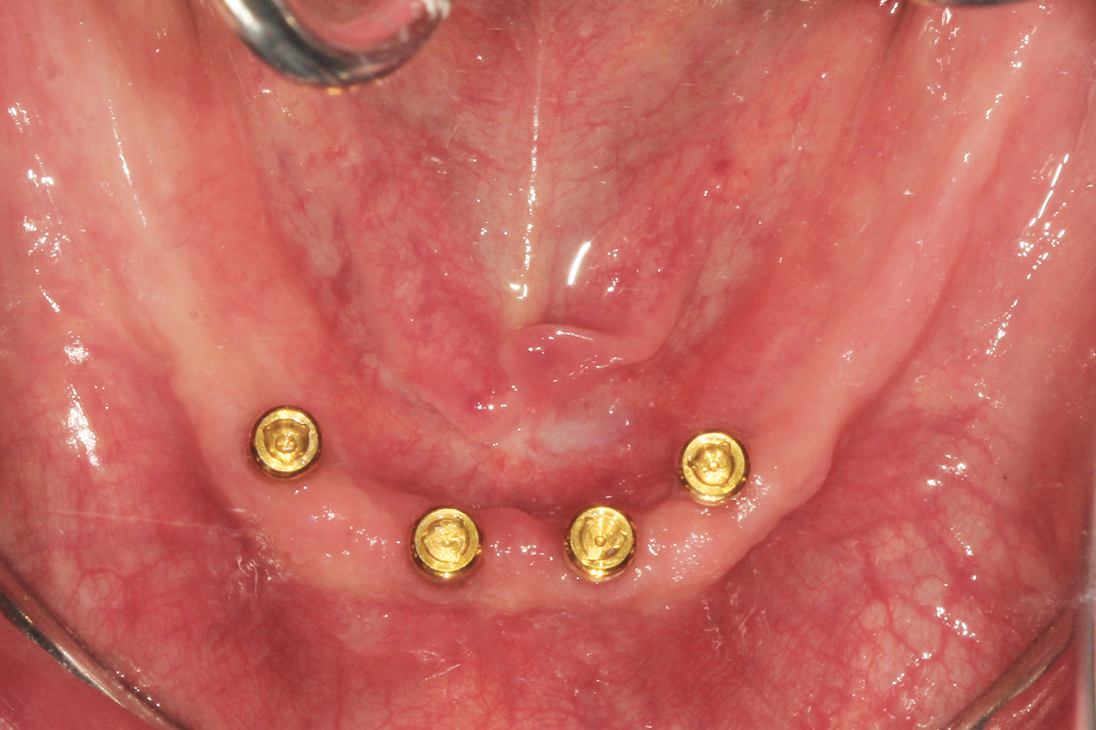

1.) Pretreatment occlusal view of the patient’s mandibular arch showing four existing implants with overdenture attachments.

Figure 1

A patient was referred to the practice by another clinician for the fabrication of a functional, stable prosthesis. He presented with four existing implants in the anterior mandible that were fitted with stud-style attachments (LOCATOR®, Zest Dental Solutions [alternatively: Stern SNAP®, Sterngold; OT Equator, Rhein83]) (Figure 1). The implants, which had been placed approximately 6 months prior, appeared healthy and well-integrated. An earlier attempt to fabricate an overdenture had resulted in an overextended prosthesis that rocked significantly. After multiple attempts to adjust the prosthesis, it had become excessively thin and ultimately fractured during function.

Capturing an ideal impression can improve the fit of the denture base and overall clinical outcome of the final prosthesis. In this case, scan bodies (LOCATOR® Scan Bodies, Zest Dental Solutions [alternatively: 3Shape Scan bodies, 3Shape; Inclusive® Titanium Scan Body, Glidewell]) were placed onto each abutment and a digital impression was captured using an intraoral optical scanner (TRIOS®, 3Shape [alternatively: Element®, iTero; Planmeca Emerald, Planmeca]) (Figure 2). The digital impression was inspected on the screen to ensure that it completely captured the edentulous ridge and the scan bodies. Next, a digital impression was made of the maxillary arch, and a third scan was performed to capture the interocclusal relationship of the two arches. A second optical impression of the mandibular arch with the patient's existing prosthesis was also captured to serve as a reference for the laboratory technician during fabrication of the new prosthesis. Finally, photographs of the patient's face in a smiling and relaxed position were acquired to assist the laboratory technician in optimizing the esthetics, midline, and phonetics of the final prosthesis.